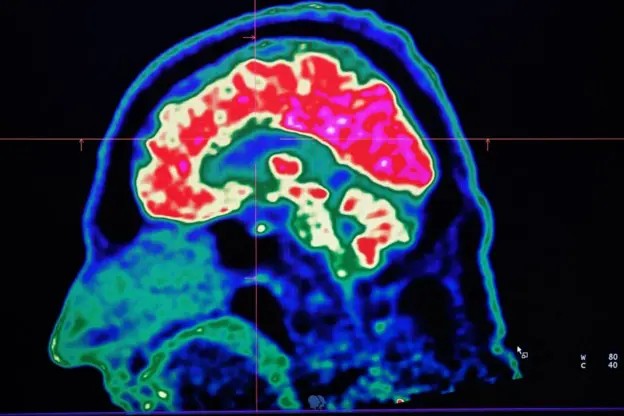

“Estava muito quente no dia e ele sofreu uma hipertermia. Testemunhamos o que achávamos ser a coisa mais assustadora que veríamos na vida”, declarou a mãe de Jake, Stephanie Smith. “Infelizmente, não foi.” As convulsões começaram a se repetir sempre que fazia calor. Com a chegada dos dias abafados e úmidos do verão, a família recorria a todo tipo de método para tentar manter Jake fresco, travando uma verdadeira batalha para conter as convulsões. Aos 18 meses, após um teste genético, Jake foi diagnosticado com a Síndrome de Dravet, uma condição neurológica que inclui um tipo de epilepsia e afeta cerca de 15 mil crianças. As convulsões costumam vir acompanhadas de deficiência intelectual e várias comorbidades, como autismo e TDAH, além de dificuldades na fala, mobilidade, alimentação e sono. O calor intenso e mudanças bruscas de temperatura podem desencadear uma crise. Veja os vídeos que estão em alta no g1 Jake hoje tem 13 anos, e já passou por incontáveis convulsões ao longo dos anos, sempre que o clima muda. “Verões cada vez mais quentes e ondas de calor têm agravado ainda mais o desafio de conviver com essa condição, que já é devastadora por si só”, afirma Stephanie. A Síndrome de Dravet é apenas uma das muitas doenças neurológicas que se agravam com o aumento das temperaturas, diz Sanjay Sisodiya, da University College London, um dos pioneiros no estudo dos impactos das mudanças climáticas sobre o cérebro. Como neurologista especializado em epilepsia, ele ouve com frequência relatos da família de seus pacientes contando que as crises pioram durante ondas de calor. “E eu pensei comigo mesmo: ‘é claro, por que as mudanças climáticas não afetariam o cérebro?’ No fim das contas, muitos processos cerebrais estão envolvidos na forma como o corpo lida com o calor.” Ao se aprofundar na literatura científica, Sisodiya descobriu uma série de condições neurológicas que são agravadas pelo aumento da temperatura e da umidade, incluindo epilepsia, acidente vascular cerebral (AVC), encefalite, esclerose múltipla, enxaqueca, entre outras. Ele também identificou que os efeitos das mudanças climáticas sobre o cérebro humano já estão se tornando visíveis. Durante a onda de calor que atingiu a Europa em 2023, por exemplo, cerca de 7% das mortes adicionais estavam relacionadas diretamente a problemas neurológicos. Percentuais semelhantes foram vistos durante a onda de calor no Reino Unido em 2022. Mas o calor também pode alterar a forma como nosso cérebro funciona, nos deixando mais violentos, irritados e depressivos. Assim, diante de um planeta que continua esquentando por causa das mudanças climáticas, qual impacto disso sobre o nosso cérebro? Cerca de 7% das mortes adicionais durante a onda de calor que atingiu a Europa em 2023 estavam relacionadas a problemas neurológicos — Foto: GETTY IMAGES Agravamento de condições neurológicas O cérebro humano, em média, raramente ultrapassa 1°C acima da temperatura corporal. Ainda assim, por ser um dos órgãos que mais consomem energia no nosso corpo, ele produz uma quantidade considerável de calor próprio enquanto pensamos, lembramos de informações e reagimos ao mundo ao nosso redor. Isso significa que o corpo precisa trabalhar duro para manter o cérebro resfriado. A circulação sanguínea, por meio de uma complexa rede de vasos, ajuda a manter essa temperatura, levando embora o calor em excesso. Isso é necessário porque as células cerebrais são extremamente sensíveis ao calor. E o funcionamento de algumas moléculas responsáveis por transmitir mensagens entre essas células também parece depender da temperatura, ou seja, elas param de trabalhar de forma eficiente se o cérebro estiver muito quente ou muito frio. “Nós não compreendemos totalmente como os diferentes elementos desse quadro complexo são afetados” diz Sisodiya. “Mas podemos pensar nisso como um relógio cujos componentes deixem de funcionar em harmonia.” Embora temperaturas extremas alterem a forma como nosso cérebro trabalha — podendo, por exemplo, afetar nossa capacidade de tomar decisões e nos levar a assumir mais riscos — quem tem alguma condição neurológica costuma ser mais gravemente impactado. A capacidade de suar pode ficar comprometida em algumas doenças neurológicas — Foto: GETTY IMAGES Isso ocorre por muitas razões. Em algumas doenças, por exemplo, a capacidade de suar pode ficar comprometida. “A termorregulação é uma função do cérebro e pode ser prejudicada se certas partes do cérebro não estiverem funcionando adequadamente”, diz Sisodiya. Já em alguns tipos de esclerose múltipla, a temperatura central do corpo parece ser alterada. Além disso, alguns medicamentos para condições psiquiátricas e neurológicas, como a esquizofrenia, afetam a regulação da temperatura, tornando a pessoa mais vulnerável à insolação ou hipertermia, como é chamada clinicamente, e aumentando o risco de morte relacionada ao calor. As ondas de calor — especialmente quando acompanhadas de temperaturas elevadas durante a noite — podem prejudicar o sono, afetar o humor e potencialmente piorar os sintomas de algumas condições de saúde. “Para muitas pessoas com epilepsia, uma noite mal dormida pode aumentar o risco de ter uma convulsão”, afirma Sisodiya. Evidências apontam que internações hospitalares e taxas de mortalidade entre pessoas com demência também aumentam durante ondas de calor. Parte disso se deve à idade — pessoas mais velhas têm mais dificuldade de regular a temperatura corporal —, mas o comprometimento cognitivo também pode dificultar a adaptação ao calor extremo. Eles podem, por exemplo, não se hidratar o suficiente, esquecer de fechar as janelas, ou sair de casa em horários que não deveriam. Aumento de casos de AVC O aumento da temperatura também tem sido associado ao crescimento de casos e mortes por AVC. Em um estudo que analisou dados de mortalidade por AVC em 25 países, pesquisadores descobriram que, a cada 1.000 mortes, os dias mais quentes contribuíam para duas mortes adicionais. “Pode não parecer muito, mas considerando que há cerca de sete milhões de mortes por AVC por ano no mundo, o calor pode estar contribuindo para mais de 10 mil mortes adicionais anualmente”, explica Bethan Davies, geriatra na University Hospitals Sussex, no Reino Unido. Ela e os coautores do estudo alertam que as mudanças climáticas tendem a agravar esse cenário nos próximos anos. Um parte desproporcional do impacto do calor em casos de AVCs recaíra sobre países de baixa e média renda — que já são mais afetados pelas mudanças climáticas e registram as maiores taxas da doença. “O aumento das temperaturas vai intensificar as desigualdades em saúde, tanto entre países quanto entre grupos sociais”, diz Davies. Um número crescente de evidências indica que pessoas mais velhas e aquelas em situação socioeconômica vulnerável correm mais risco de morrer em decorrência do calor externo. Partos prematuros O mundo mais quente também está afetando o neurodesenvolvimento dos mais jovens. “Existe uma ligação entre calor extremo e resultados adversos na gravidez, como partos prematuros”, afirma Jane Hirst, professora de Saúde Global da Mulher no Imperial College London. Uma revisão sistemática recente da literatura científica concluiu que ondas de calor estão associadas a um aumento de 26% na ocorrência de partos prematuros, que podem levar a atrasos no desenvolvimento neurológico e prejuízos cognitivos. “No entanto, há muitas coisas que a gente ainda não sabe”, acrescenta Hirst. “Quem é mais vulnerável e por quê? Afinal, há 130 milhões de mulheres que tiveram bebês este ano, muitas delas em países quentes, e isso não acontece com elas.” O calor excessivo causado pelas mudanças climáticas também pode sobrecarregar o cérebro, deixando-o mais vulnerável a danos que podem levar ao desenvolvimento de doenças neurodegenerativas. O calor ainda afeta a barreira hematoencefálica, que normalmente protege o cérebro, tornando-o mais permeável e aumentando o risco de que toxinas, bactérias e vírus entrem no tecido cerebral. Essa questão pode se tornar ainda mais crítica à medida que as temperaturas sobem, já que o aumento de calor favorece a expansão de mosquitos que transmitem vírus capazes de causar doenças neurológicas, como Zika, chikungunya e dengue. “O vírus Zika pode afetar o feto e causar microcefalia”, explica Tobias Suter, médico entomologista do Instituto Suíço de Saúde Pública e Tropical. “Com o aumento das temperaturas e invernos mais amenos, a temporada de reprodução dos mosquitos começa mais cedo no ano e termina mais tarde.” Ondas de calor podem influenciar em vários fatores, desde a atividade elétrica das células nervosas até o risco de suicídio, ansiedade climática e a estabilidade de medicamentos usados no tratamento de condições neurológicas. Mas os efeitos das altas temperaturas sobre o cérebro ainda estão sendo investigados pelos cientistas. O calor afeta as pessoas de diferentes formas — algumas se adaptam bem, enquanto outras consideram insuportável. “Vários fatores podem explicar essa sensibilidade diferente, e um deles pode ser a predisposição genética”, afirma Sisodiya. Variações genéticas podem influenciar as estruturas de proteínas que deixam algumas pessoas mais vulneráveis aos impactos das mudanças climáticas. “Pode haver fenótipos termo-latentes que apenas irão se manifestar quando essas pressões ambientais forem suficientes para trazê-los à tona”, disse. “O que estamos observando hoje nas pessoas com distúrbios neurológicos pode se tornar relevante para pessoas sem distúrbios neurológicos à medida que as mudanças climáticas avançam.” Ainda há muitas perguntas sem resposta. É a temperatura máxima, a duração da onda de calor ou a temperatura noturna que tem o maior impacto sobre o cérebro? A resposta pode variar de pessoa para pessoa ou de acordo com a condição neurológica. Mas identificar quem está em risco e por quê é essencial para desenvolver estratégias para proteger os mais vulneráveis. Isso pode incluir a criação de sistemas de alerta precoce ou seguros que compensem trabalhadores pela perda de renda em dias de calor extremo. “A era do aquecimento global acabou, a era da ebulição global chegou”, anunciou o secretário-geral da ONU, António Guterres, quando julho de 2023 foi confirmado o mês mais quente já registrado. As mudanças climáticas estão entre nós e se intensificando. A era do cérebro “superaquecido” está apenas começando.